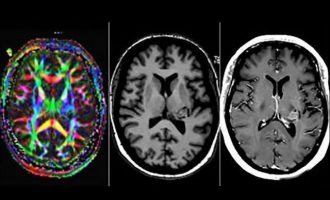

Γυναίκα που «της μίλαγε ο Θεός» αποδείχτηκε ότι είχε όγκο στον εγκέφαλο

Μια γυναίκα που ισχυριζόταν ότι άκουγε τον Θεό να της μιλάει, αποδείχτηκε ότι είχε όγκο στον εγκέφαλο. Η γυναίκα ήταν…